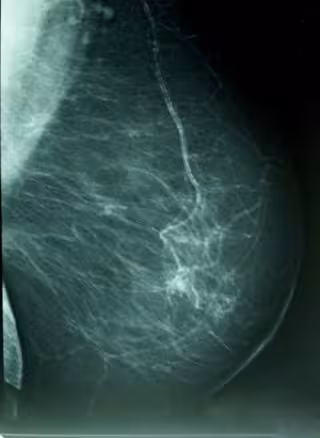

Cáncer De Mama, Densidad Mamográfica

WIKIPEDIA/A. AVENDAÑO

"Osakidetza desde 1995 realiza una mamografía cada dos años a las mujeres de entre 50 y 69 años, y las charlas tratan de sensibilizar sobre la importancia de la educación en la salud y tratan de animar a las mujeres a participar en ese programa", ha afirmado.